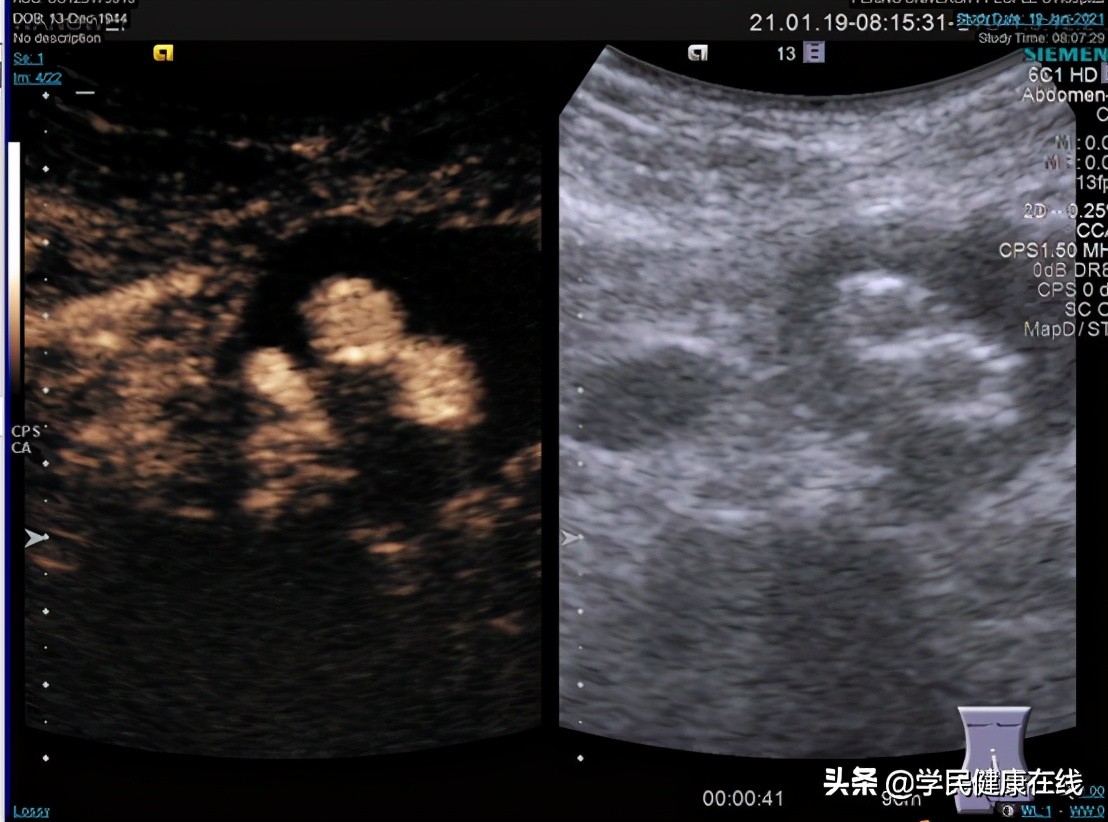

图5. 术前超声造影,可见后壁有造影剂进入

图6. 术后造影,已无明显造影剂进入瘤囊

2021年1月22日,在手麻科和泌尿外科叶雄俊、刘军医生的帮助下,我们两个科室合作完成了全国首例腹腔镜下EVAR术后II型内漏的处理,术中根据术前的影像分析,很快定位到肠系膜下动脉和两对腰动脉,一根骶正中动脉,分别夹闭切断。术前充分的准备,术中没有意外发生,手术顺利完成。术后复查超声造影,证实已无造影剂漏入瘤囊。